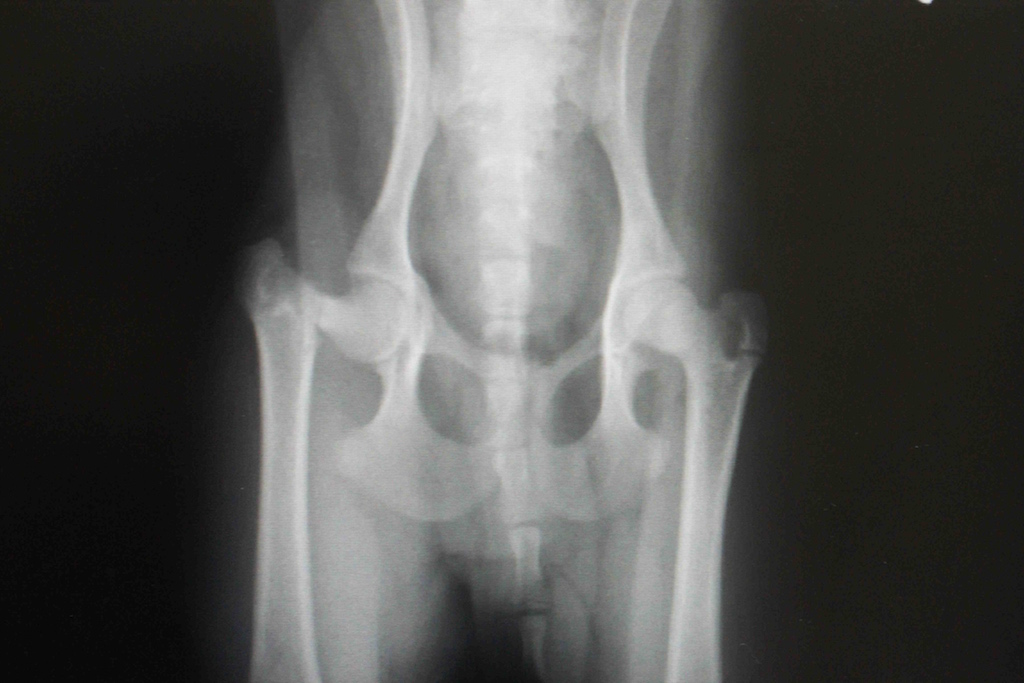

Votre animal a subi une fracture du col fémoral, c’est-à-dire une fracture de l’os de la cuisse à l’endroit où il s’articule avec le bassin. Malheureusement, un plâtre ne peut pas être utilisé pour stabiliser cette fracture, car il est impossible d’immobiliser la hanche. Par conséquent, une intervention chirurgicale a été nécessaire afin de retirer la partie du fémur encore attachée à l’articulation.

Après l’opération, une image post-opératoire montre que la tête du fémur a été retirée. Heureusement, cette chirurgie offre un excellent pronostic, en particulier pour les petits animaux. En effet, ce sont les muscles entourant l’articulation de la hanche qui vont assurer la stabilité du site de fracture et permettre à votre compagnon de retrouver une démarche normale. Plus il utilisera rapidement sa patte, plus ses muscles se renforceront et plus vite la boiterie disparaîtra. En moyenne, il faut environ un mois pour que la guérison soit complète.